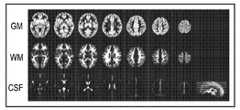

도 6a 및 도 6b는 뇌 조직을 분류하고 불균질성을 보정하기 위한 처리들을 예시한다. 예로서, 도 6a는 회색질(GM), 백색질(WM) 및 뇌척수액(CSF)으로 분류된 뇌의 상이한 구조체들을 표시한다. 도 6b에서, 원본 영상의 예가 도면의 상부에 도시되고, 제시된 기술에 따라 불균일성을 보정한 이후가 도면의 하부에 도시된다. 바람직한 실시예에서, 이들 처리들 양쪽 모두는 하나의 퍼지 C-평균 클러스터링(fuzzy C-means clustering) 프레임워크에 통합된다. 본 기술분야의 통상의 기술자는 퍼지 클러스터링 평균(C-평균)이, 클러스터들에 대한 데이터 포인트들의 할당이 고정되지 않거나 "어렵지만"(전부냐 또는 전무냐(all-or-nothing)), 퍼지 로직으로 이해되는(예를 들어, 발견적으로(heuristically) 결정되는) 것과 동일한 성질로 "퍼지"한 클러스터링 분석을 제공하는 알고리즘들의 클래스임을 인식할 것이다.Figures 6A and 6B illustrate treatments for classifying brain tissue and correcting for heterogeneity. By way of example, Figure 6a depicts different structures of the brain classified as gray matter (GM), white matter (WM) and cerebrospinal fluid (CSF). In Fig. 6B, an example of the original image is shown at the top of the figure, and after the correction of the non-uniformity in accordance with the presented technique is shown at the bottom of the figure. In a preferred embodiment, both of these processes are integrated into a single fuzzy C-means clustering framework. One of ordinary skill in the art will appreciate that the fuzzy clustering average (C-average) may be used to determine whether the allocation of data points to clusters is not fixed or " difficult " (all-or- Quot; fuzzy " clustering analysis with the same properties as those that are understood (e.g., heuristically determined).